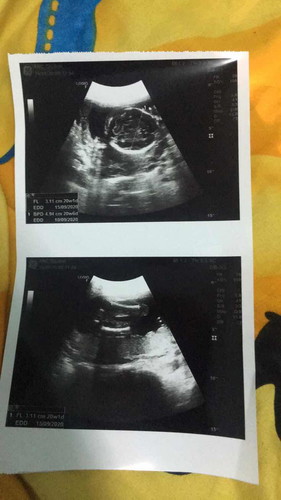

ใบอัตราซาวด์

ขออนุญาตสอบถามคุณแม่นะคะช่วยดูให้หน่อยว่าเพศหญิงหรือเพศชายหรอคะ

ซูมแล้วก็ดูไม่ออกเลยค่ะแม่😅